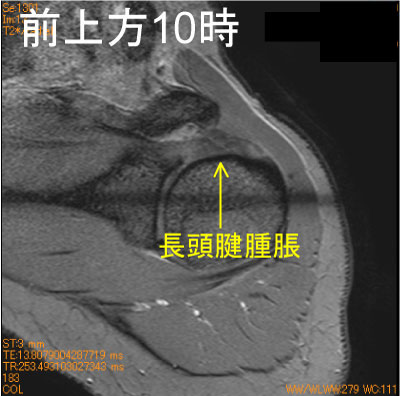

長頭腱腫脹 外傷後-肩関節MRI-

30代女性、スケートで転倒、関節腔内での長頭腱腫脹を認めている。

MRIで長頭腱はそれなりに観察出来る。

必ず長頭腱も観察する習慣を持って、正常長頭腱像を脳裏に焼き付いていないと見落とす。